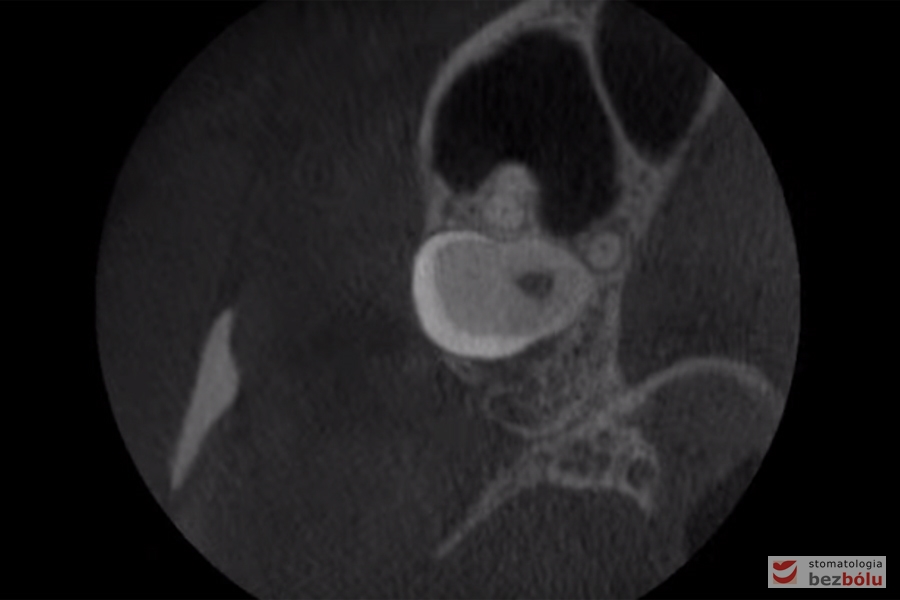

Diagnostyka tomograficzna - w celu określenia położenia korzeni dla mikrośruby ortodontycznej

Diagnostyka tomograficzna – w celu określenia położenia korzeni dla mikrośruby ortodontycznej